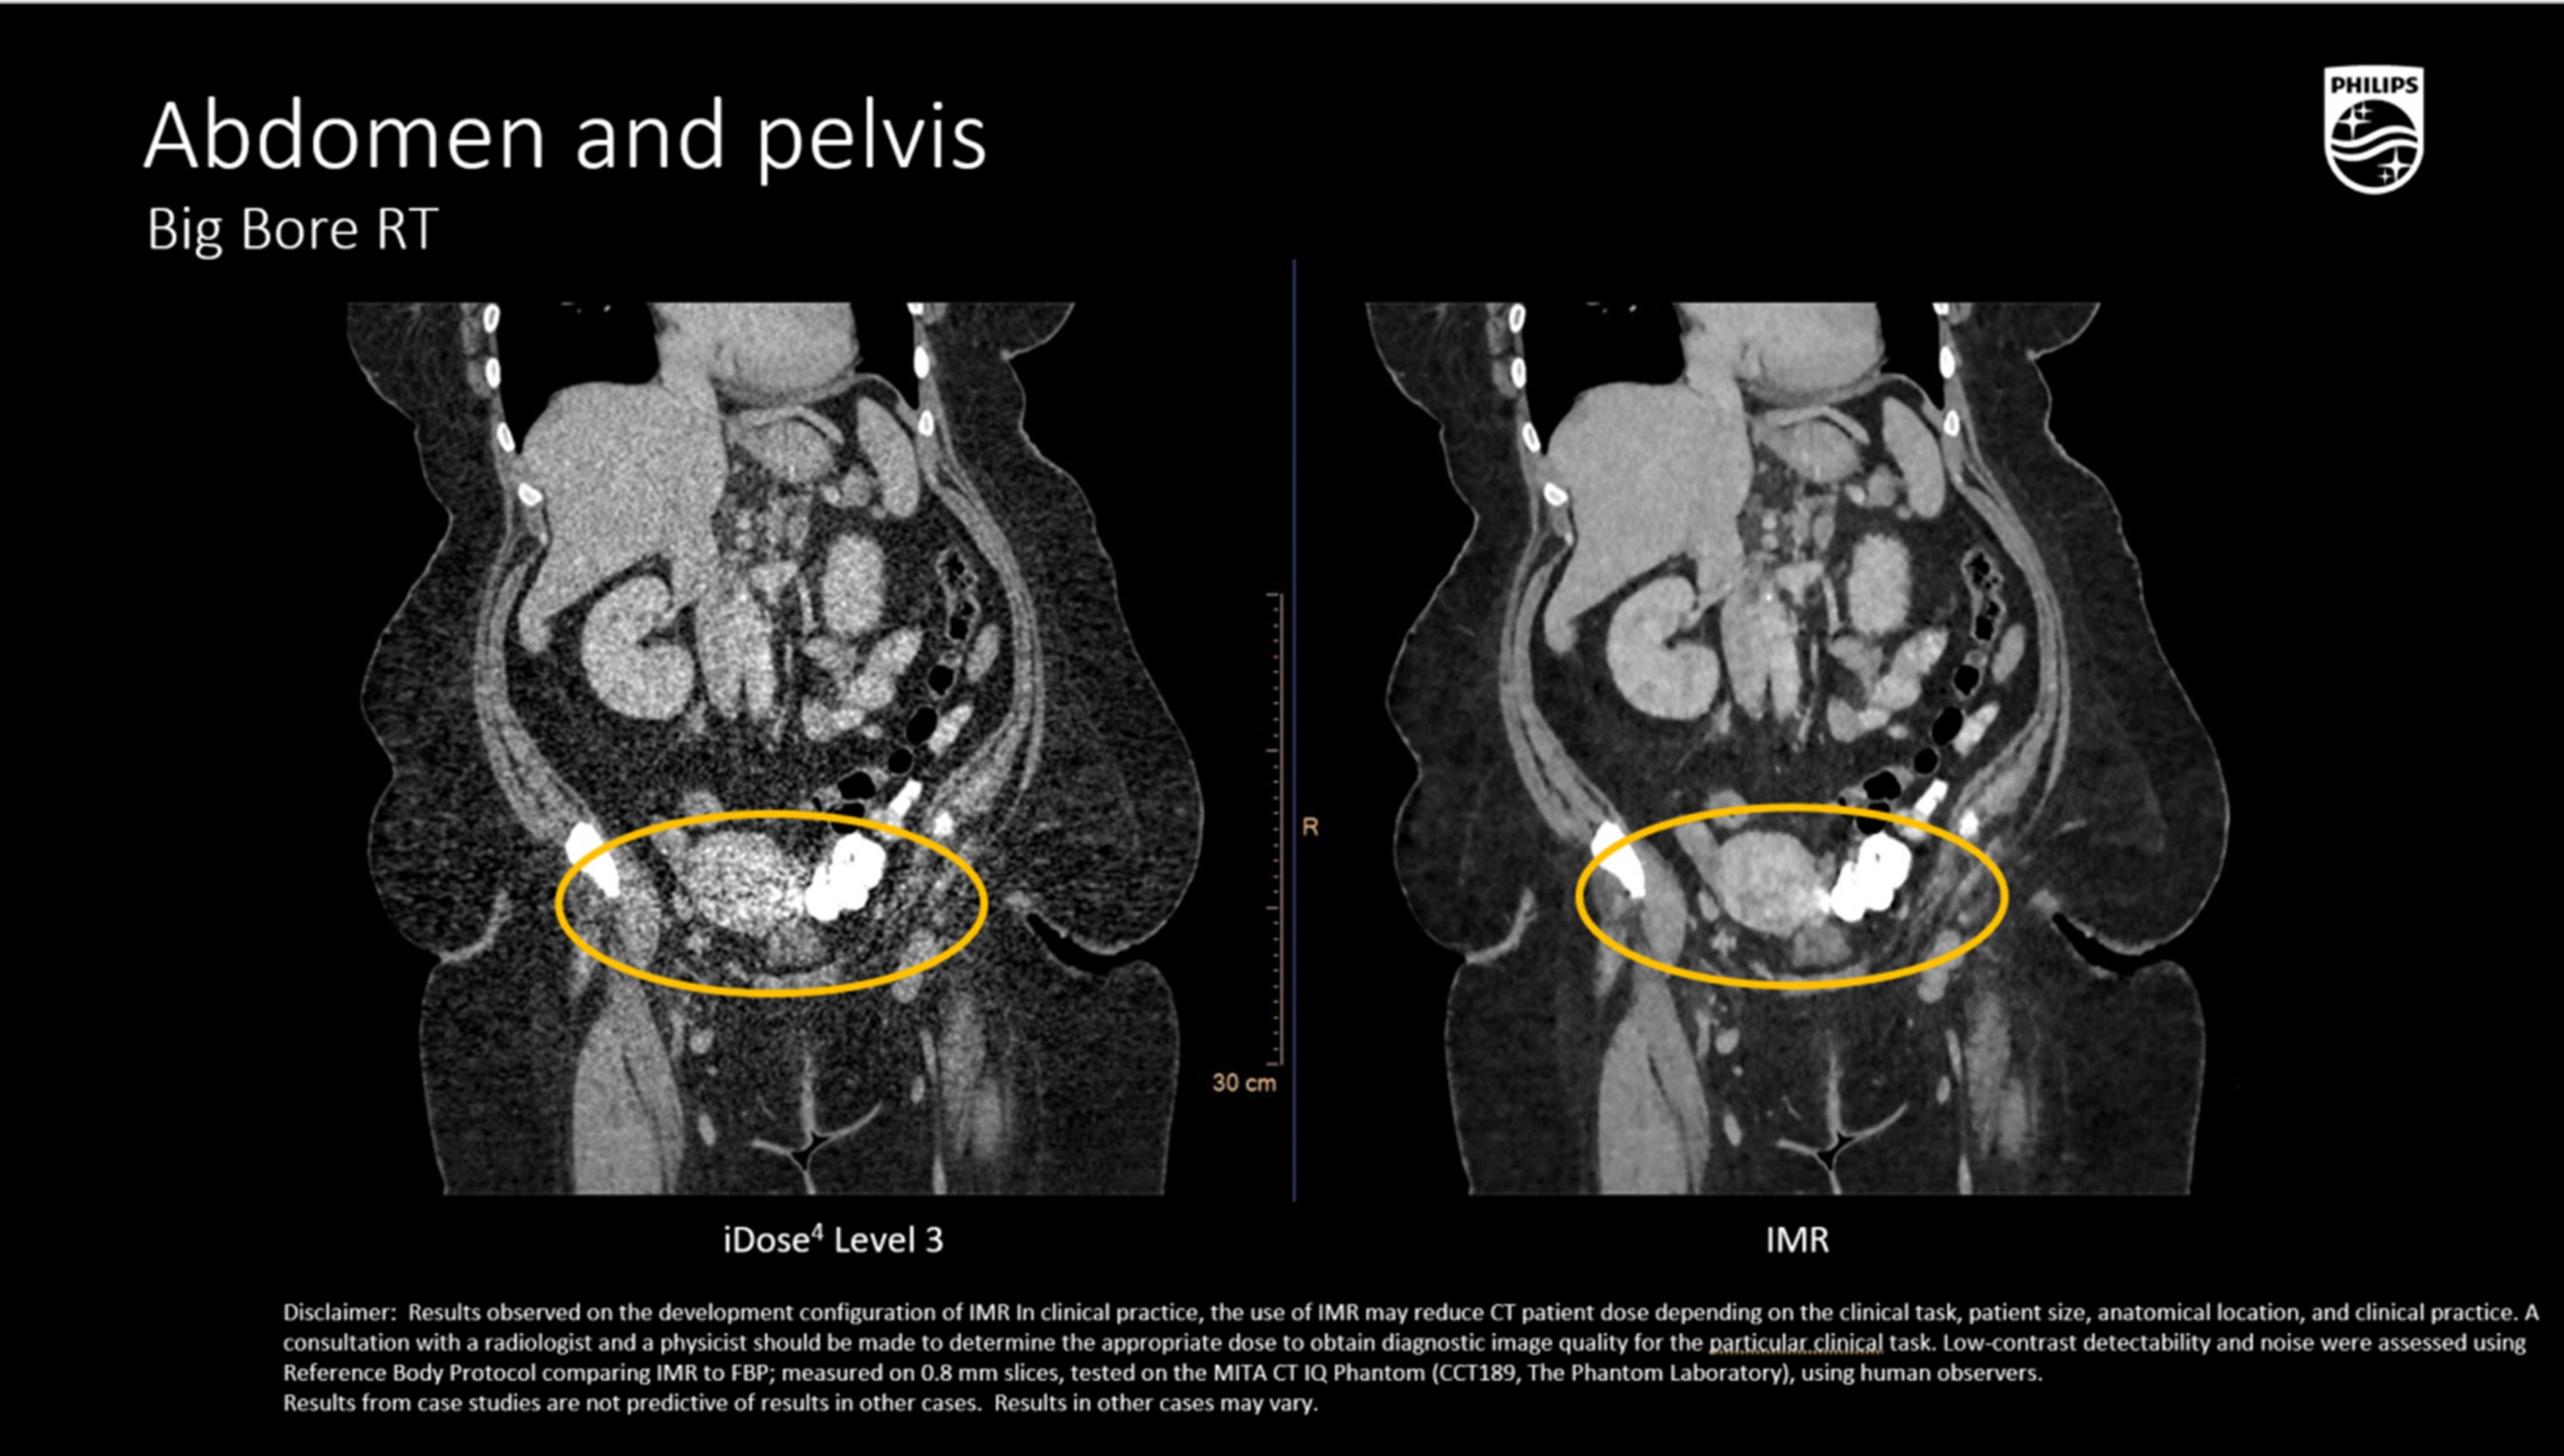

O-MAR (Orthopedic Metal Artifact Reduction)

- Комплексный алгоритм для снижения артефактов от эндопротезов, спиц, хирургических скоб и зондов,

- Существенно повышает точность КТ-контурирования в условиях металлоиндуцированных искажений, что критично для радиотерапии позвоночника и малого таза.

Абдоминальная и тазовая локализация

- Визуализация мягкотканных опухолей (печень, почка, поджелудочная железа, органы таза) с контурированием OAR,

- Возможность КТ-анализов с контрастированием в артериальную, венозную и позднюю фазы,

- Использование для расчета смещения мочевого пузыря и прямой кишки в динамике.